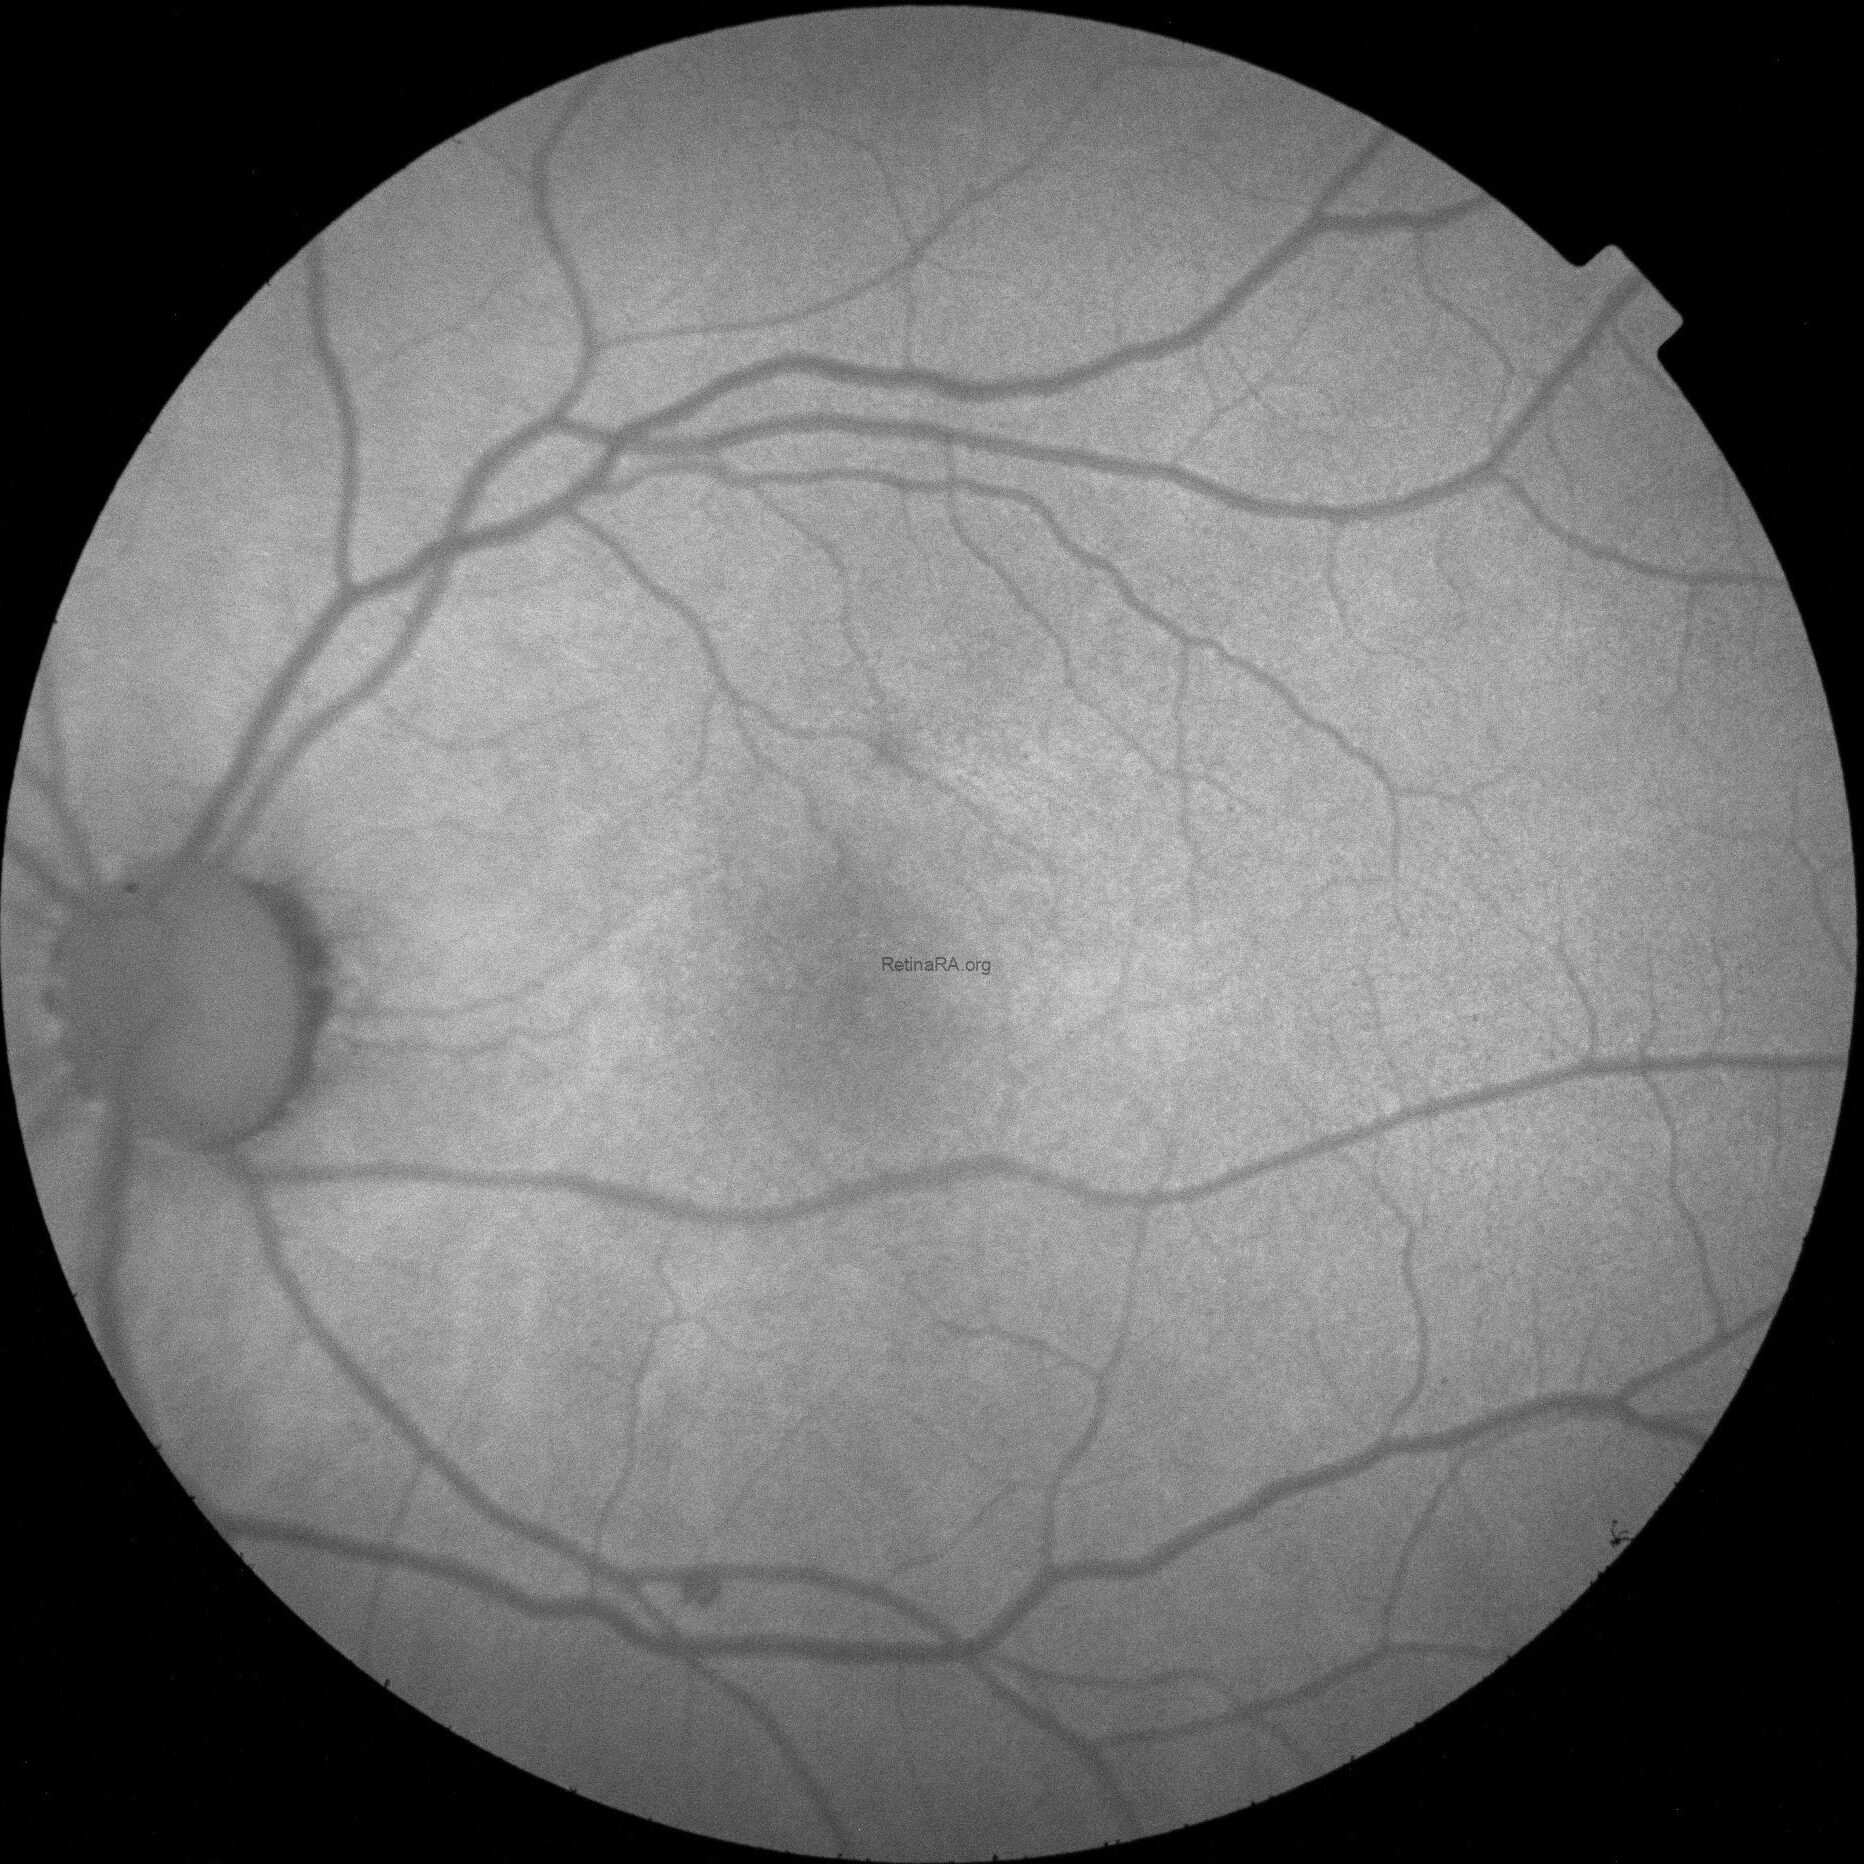

These findings are better highlighted with red-free photography, which demonstrates a full encircling of the fovea by the anomalous reflex and furthermore displays extensive RNFL defects in the left eye when compared to the right eye.

FAF in OS was normal.